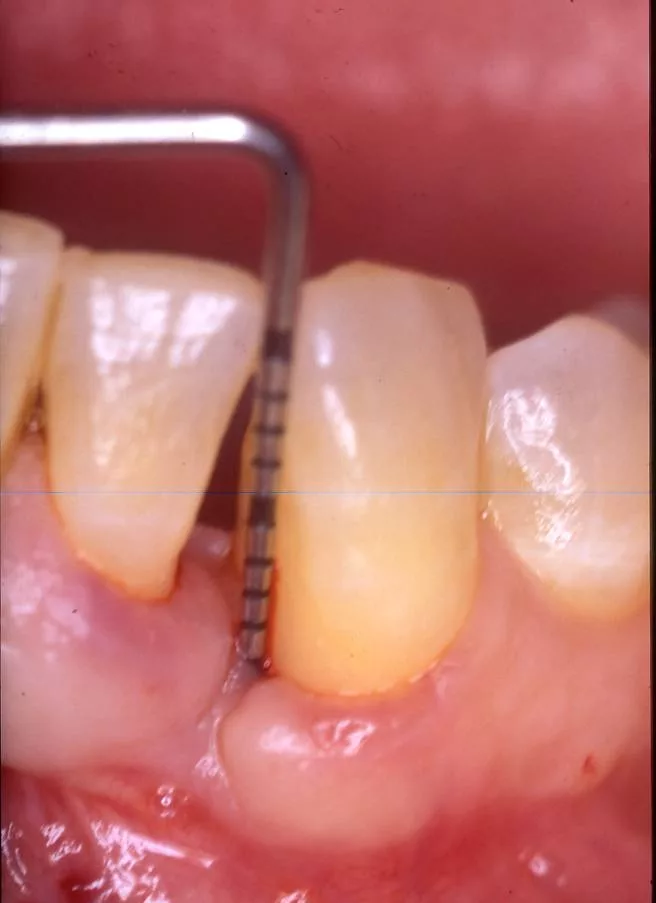

• Réduire la présence de poches supérieures à 6 mm car le risque de progression de la maladie est élevé

• Éliminer le saignement, témoignage de la présence d’un tissu inflammatoire résiduel sous la gencive

Des techniques chirurgicales de préservation papillaire permettent de régénérer les tissus parodontaux en garantissant leur maintien esthétique. Ces techniques chirurgicales avancées s’effectuent sous aides optiques grossissantes et avec des instruments micro chirurgicaux spécifiques.